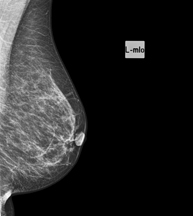

Digital mammography

Digital mammography is an innovative breast examination technique that uses a low radiation dose, thus reducing exposure compared to conventional mammography. The image is digitised using special cassettes on a system known as CR (Computed Radiography). These digitalisation techniques provide excellent images, especially in breasts that are difficult to examine, such as glandular breasts, which appear dense on mammograms, enabling better detection of tumours in this group of patients.